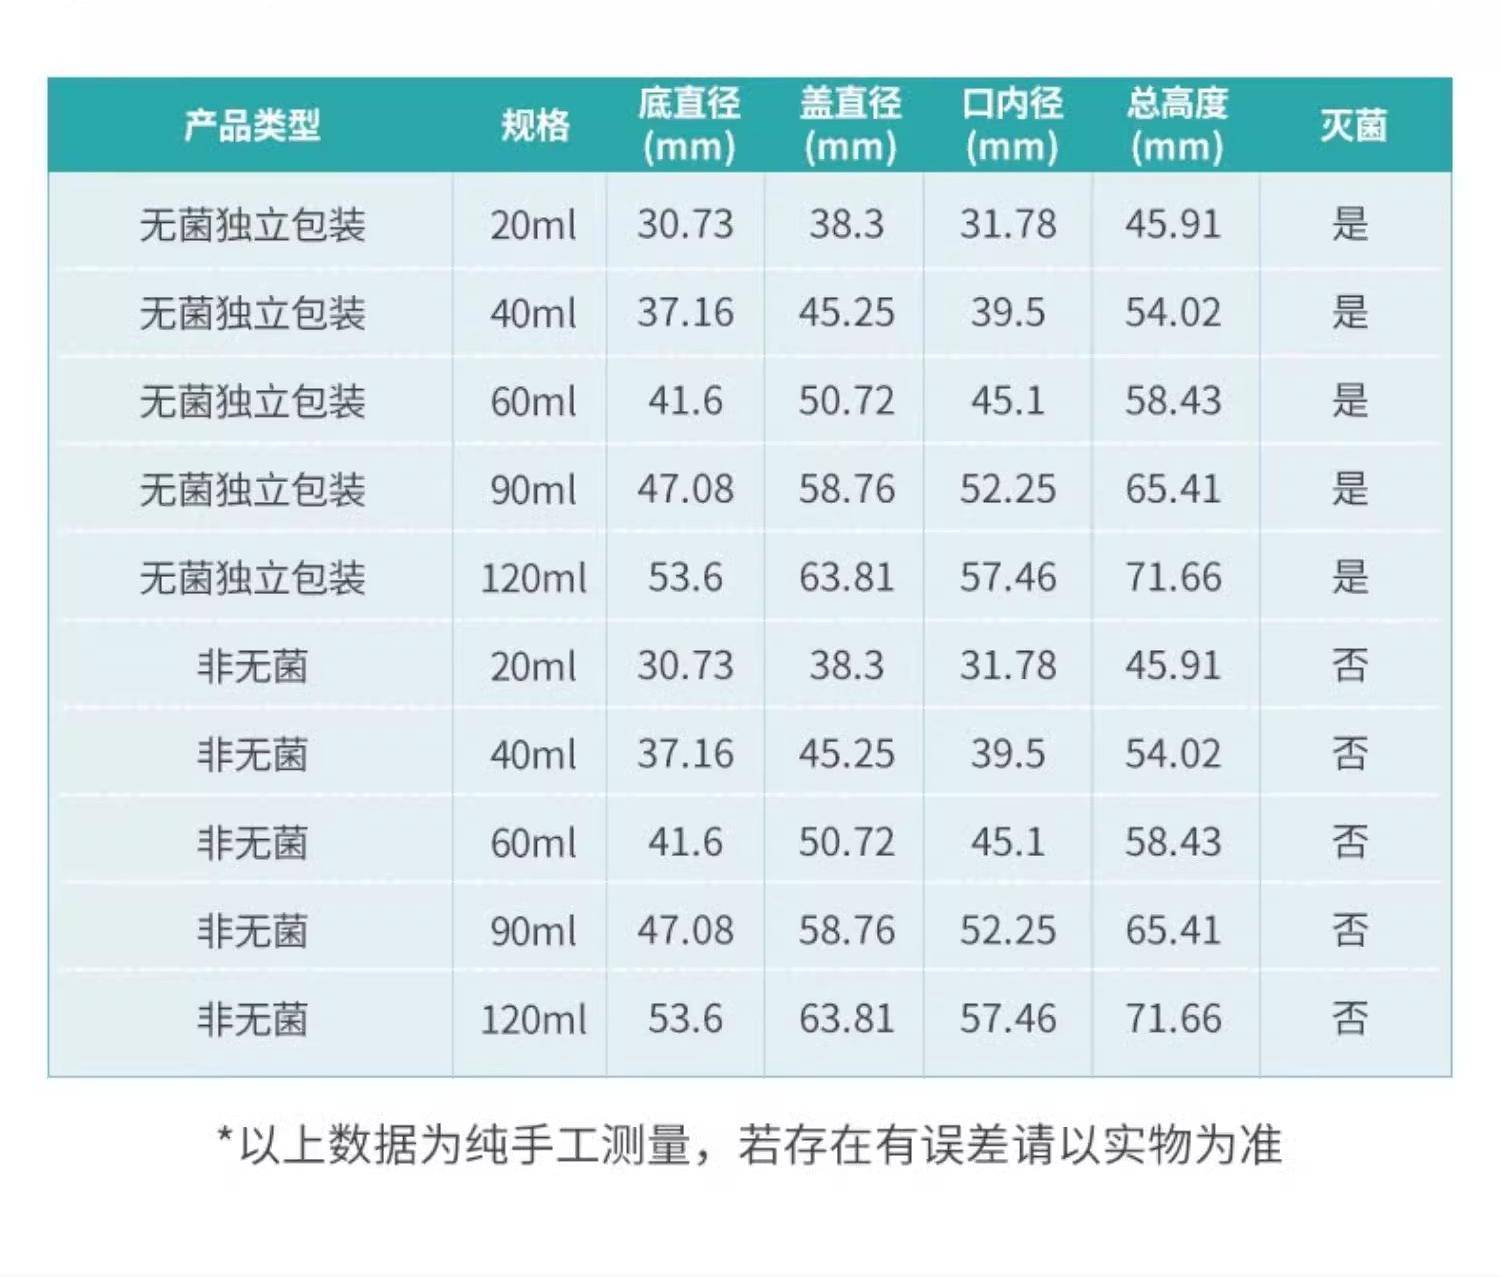

bkmamlab 采樣杯/樣品杯/尿杯40ml(蓋)